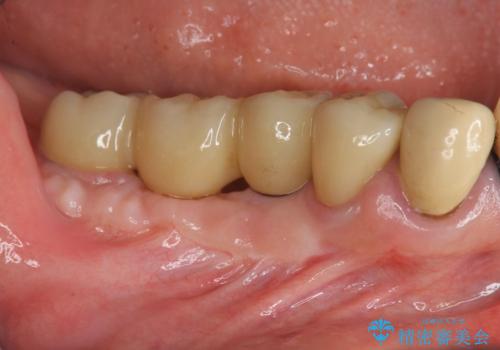

遊離歯肉移植術(硬い歯ぐきのインプラント周囲への移植)を行ったことで、炎症に強く歯ブラシのしやすい環境をインプラント周囲に整えることができました。